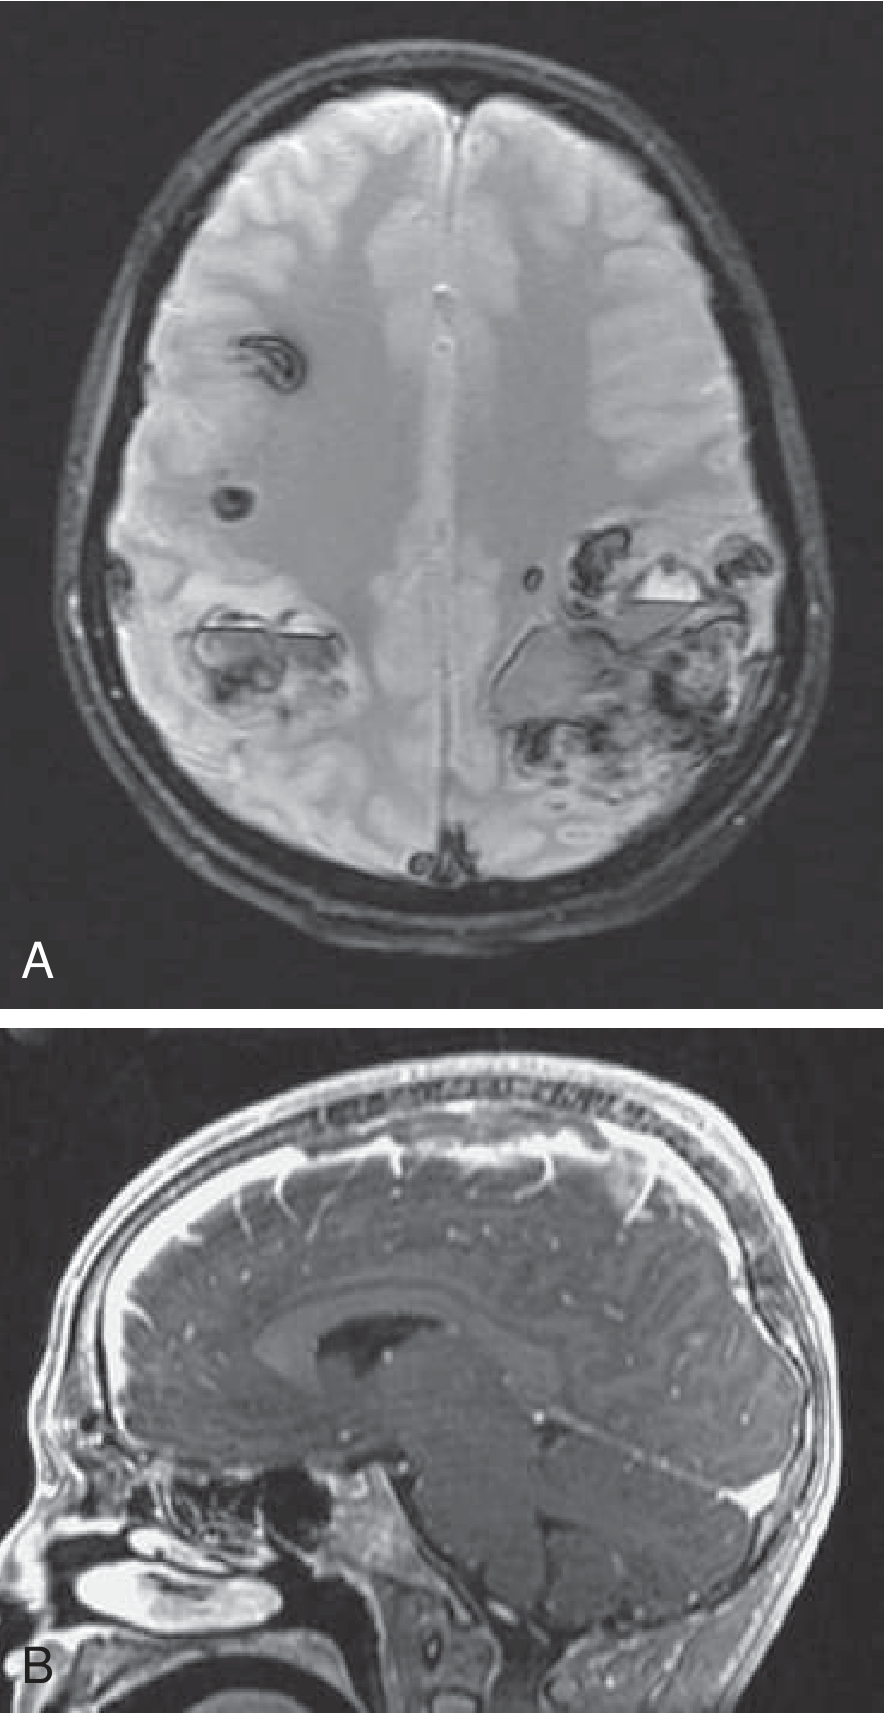

Fig. 65.36 — Bilateral hemorrhagic parietal infarctions (GRE, Panel A) and MRV showing SSS thrombosis (sagittal, Panel B) in a 14-year-old on L-asparaginase therapy:

GRE MRI showing bilateral hemorrhagic parietal infarctions (A) and sagittal MRV showing SSS thrombosis (B)